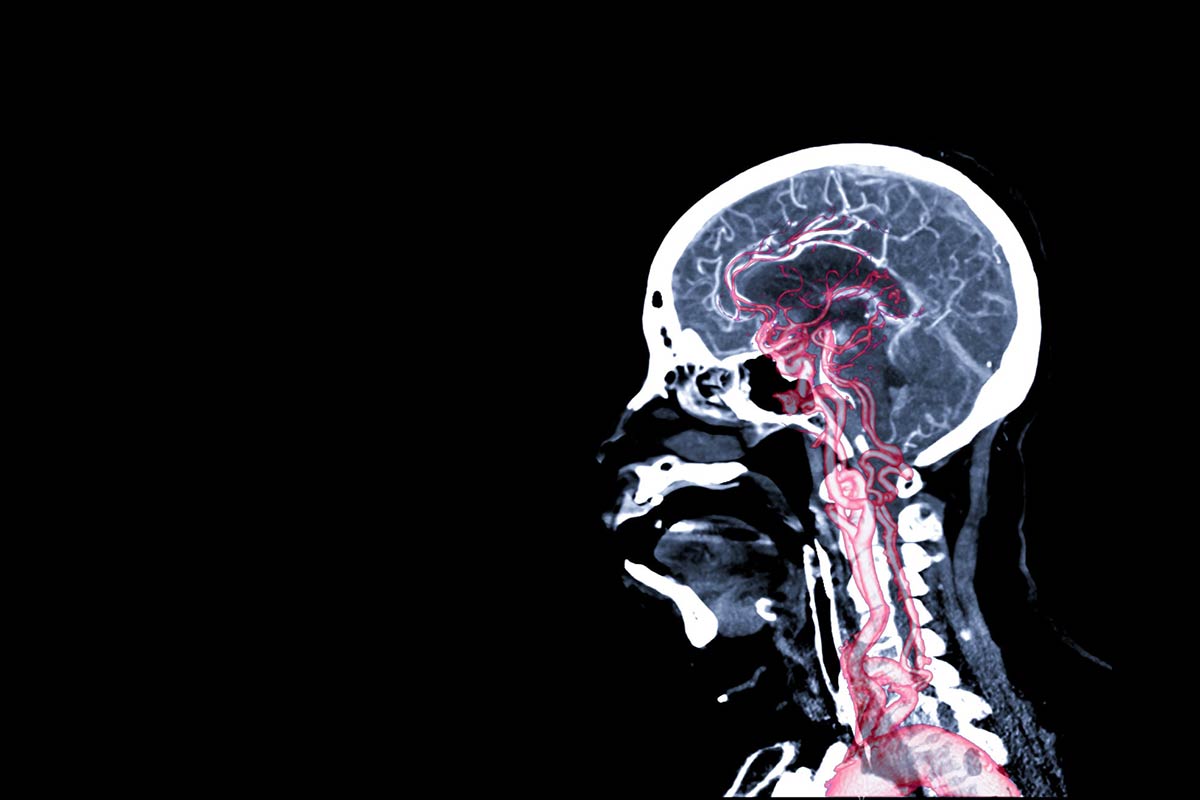

Have you ever wanted to find out information about your brain? You could measure the intracranial pressure, understand the anatomy, and catch conditions early.

Bioresorbable pressure sensors have ultrathin silicon and silica. These light materials allow the device to monitor intracranial pressure, which is the amount of pressure that is inside of the skull.